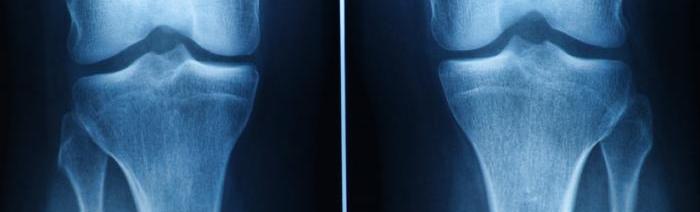

Understanding Cartilage and Its Damage

Cartilage is crucial for joint function, providing cushioning and flexibility. Damage, whether from trauma or conditions like osteoarthritis, reduces its effectiveness.